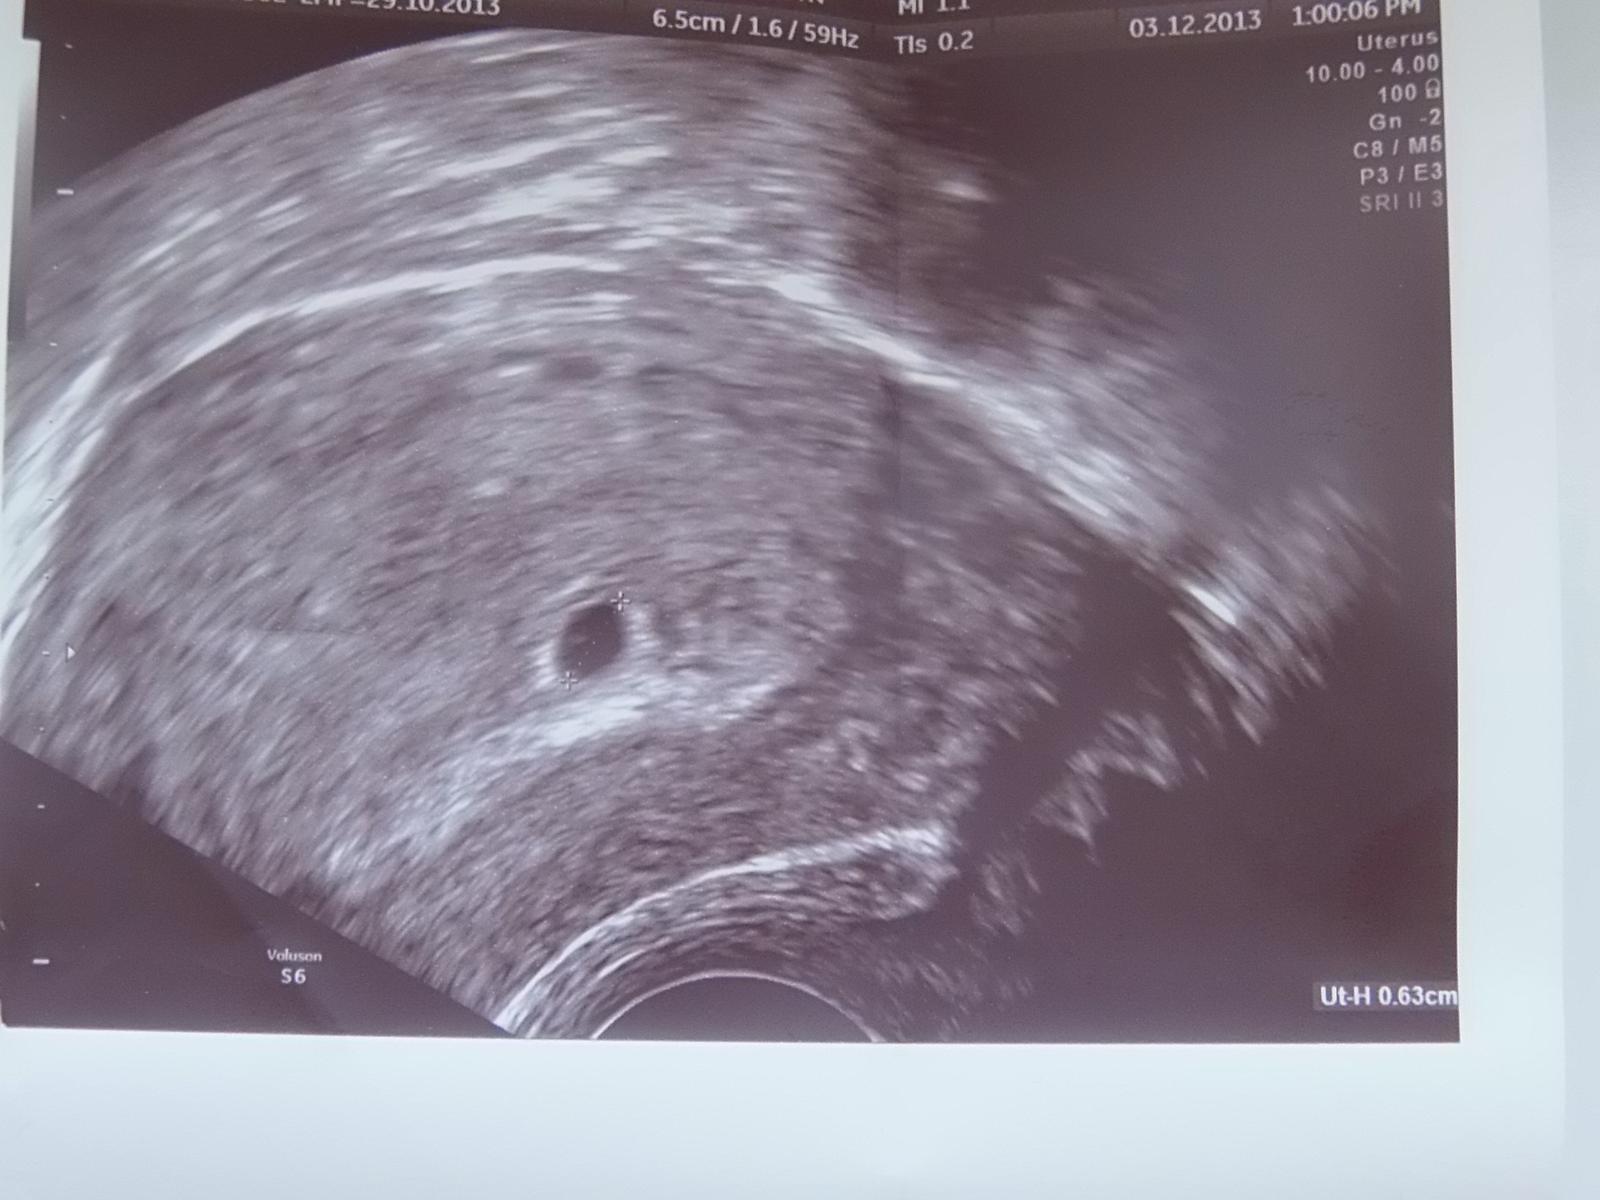

ahojte baby. aj ja sa k vám pridávam, zatiaľ len tak potichučky. podľa tehu kalkulačky by to malo byť 6.8. dnes som bola u dokyho, na sono skoro nič ešte nebolo vidno, len že začínajúca gravidita, ale.....od dnes si musím pichať fraxiparin celé tehu. najbližšia kontrola v sobotu 21.12. to by už mala byť aj akcia srdiečka.

ja absolútne netuším aké majú byť hodnoty HCG. v stredu na sone mi nič nebolo vidno. v piatok už videlo gestačný vak o veľkosti 4,4mm.